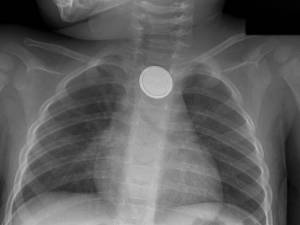

With the increase in these devices and the constant demand for more powerful batteries to power them, the problem of accidental ingestion is increasing. In 2013, there were more than 3,000 reported cases of unintentional battery ingestion, the majority in children under the age of 6.

“Ingested disc batteries require emergent removal from the esophagus,” says co-first study author Giovanni Traverso, MB, BCh, Ph.D., a gastroenterologist at Massachusetts General Hospital and a researcher at MIT. “The swallowing of these batteries is a gastrointestinal emergency given that tissue damage starts as soon as the battery is in contact with the tissue, generating an electric current and leading to a chemical burn.”